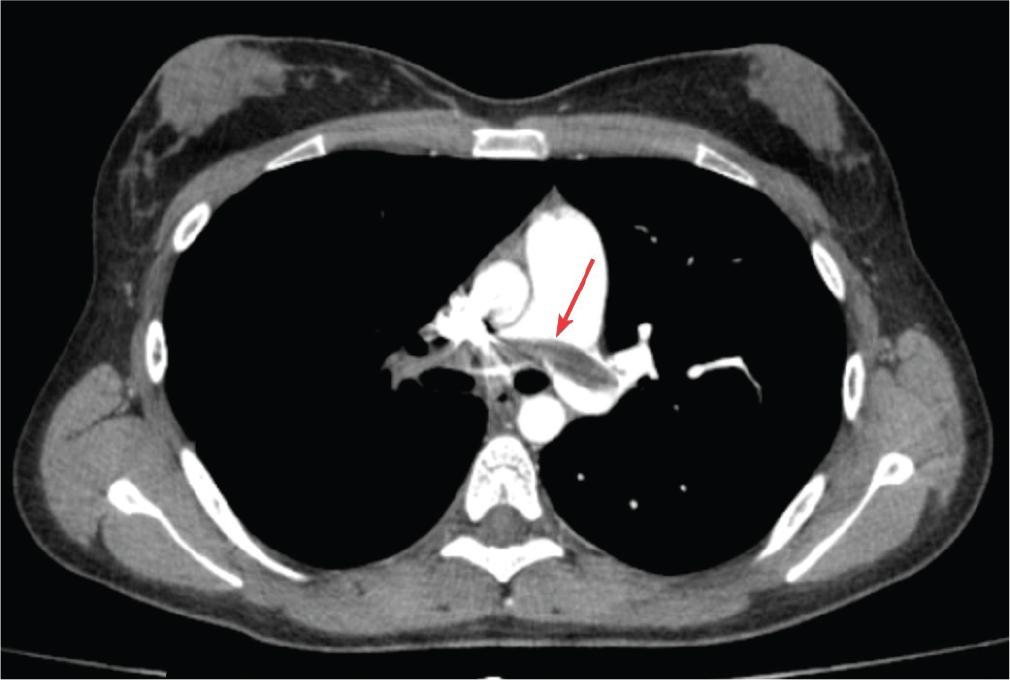

Figure 3.